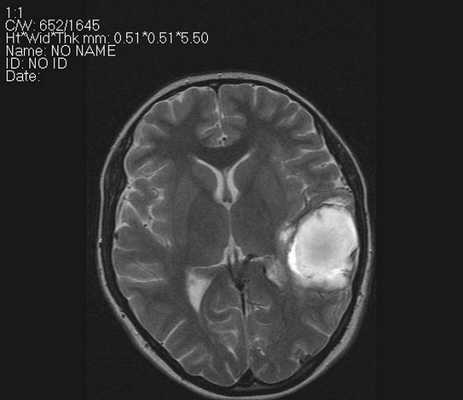

Очаги ишемии на МРТ

Очаги ишемии

Нарушения мозгового кровообращения приводят к кислородному голоданию тканей, что может спровоцировать их некроз (инфаркт). Ишемические очаги при Т2 взвешенных последовательностях выглядят как зоны с умеренно гиперинтенсивным сигналом неправильной формы. На более поздних сроках при проведении в Т2 ВИ или FLAIR режиме МРТ единичный очаг приобретает вид светлого пятна, что указывает на усугубление деструктивных процессов.

некроз церебрального вещества (гиперинтенсивный очаг на Т2-взвешенных изображениях);

Острый период (1-7 день) характеризуется появлением четко ограниченных светлых участков на МРТ в Т2-взвешенном режиме. На Т1 ВИ очаги некроза имеют гипоинтенсивный сигнал.

Монохромные изображения позволяют выявить измененные участки, которые отличаются по цвету от здоровых тканей. Очаги ишемии и кровоизлияния имеют четкие границы, позволяя уточнить степень поражения мозговых структур.

Инфаркт головного мозга на МРТ